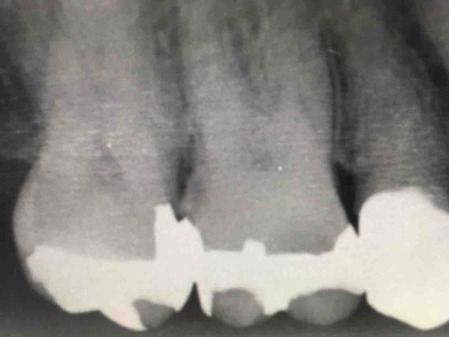

毎日、毎日、歯石を除去する毎日(^^)

見えるって凄い!!大変だけど結構好きです。見えない世界の歯石をとるの♡

全て除去してこうなります↓

なかなか写真や動画を編集できませんが、毎日処置を行っています。